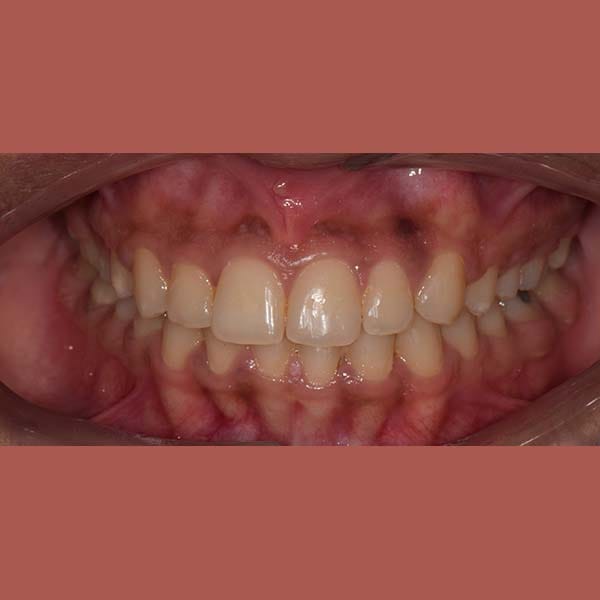

BEFORE

Our young friend suffered from insufficient spaces for her teeth to align properly, which caused her a reverse bite in some of the front teeth.

She also suffered from a severe gummy smile and had a gap resulting from the extraction of an upper molar.

And because she didn’t want to use dental implants, we had to close the gap by moving the molars located behind it forward. This made the situation more difficult and complicated

The teeth overlay was treated orthodontically by means of fixed braces and without any tooth extraction. We also pulled the posterior molars forward to close the gap successfully, and the gummy smile was almost solved without the need for surgery.